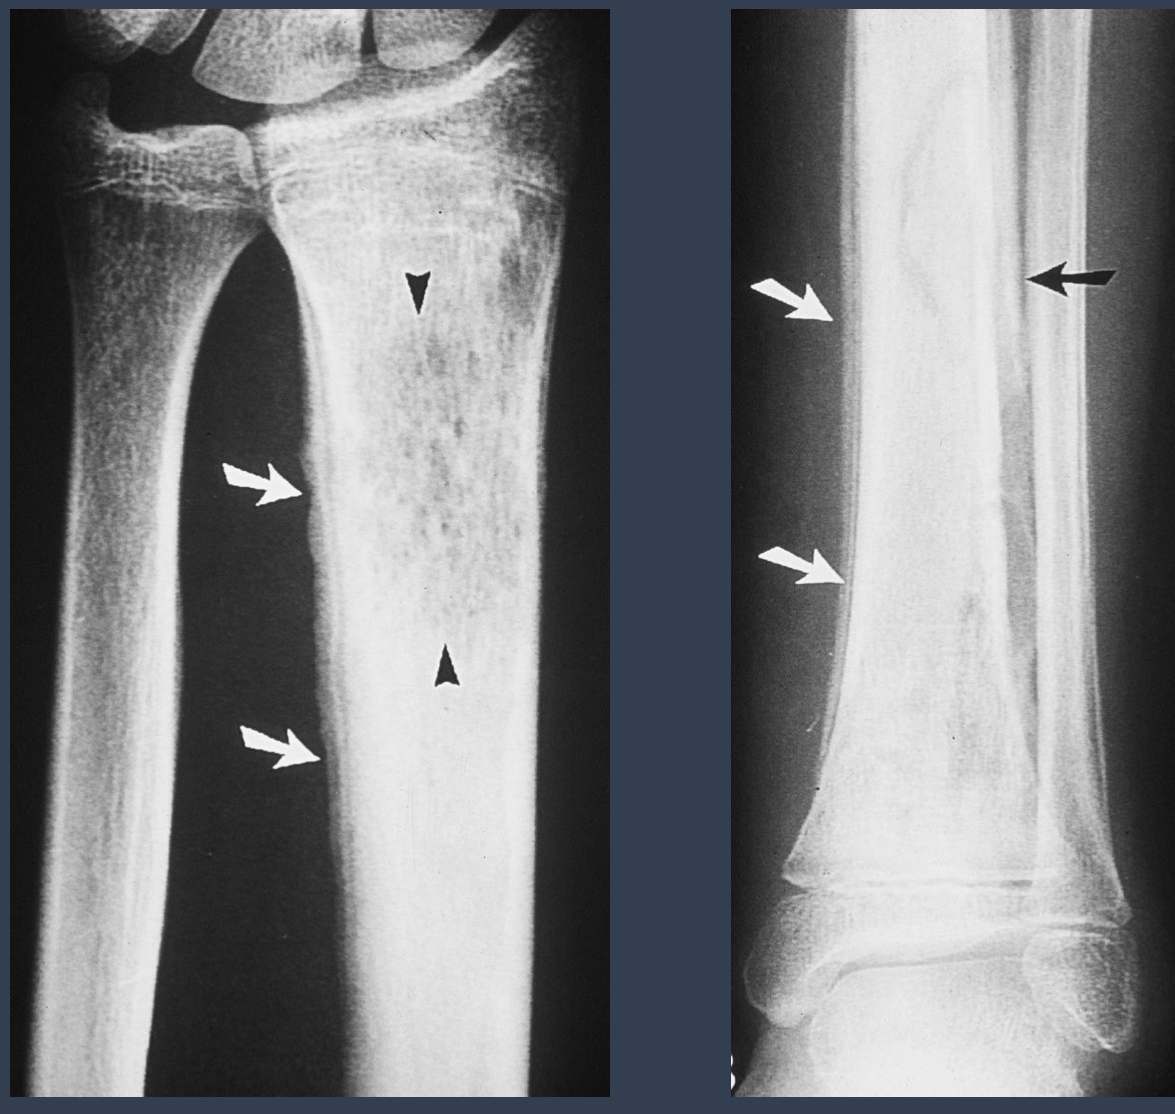

what is this condition?

oseomyelitis

what are the arrows pointing to?

sequestrum = island of dead bone

what is noteable in the long bone?

involucrum = thick layer of periosteal new bone that forms around sequestrom

what is the opening from the bone to the skin called that may show up in this patient?

cloaca = opening in an involucrum that drains pus and debris out of infected bone

via sinus tract